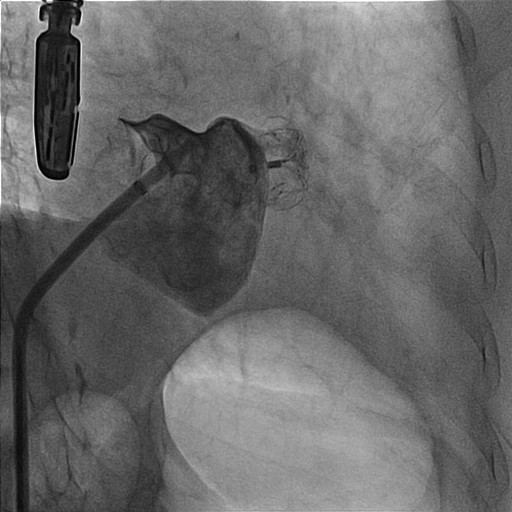

1. We made right femoral vein puncture and inserted 8 Fr sheath. Then we advanced the SL0 catheter to atrial septum.2. We used BRK transeptal needle to perform transeptal puncture under TEE guidance and advanced the dilator and SL0 catheter.3. The LAAO size was chosen under TEE and under angiography and we selected the 20/26 mm Lambre LAA Closure System (Lifetech Scientific).4. We deployed the LAA occlude. But the position of the LAAO changed soonly and unstable after the deployment under angiography and TEE view. (Image 1) (Video 1) 5. The procedure was going to be closed. However, the LAAO disappeared under the TEE view and dislodged to the aortic arch at the next moment. 6. SJM 12 Fr sheath (Abbott) was inserted through right femoral artery and we chose a JR4 8 Fr. guiding catheter. We used the JR4 to crush the LAAO at first.7. Then we used the AndraSnare (Andramed) to catch the device and pulled it to the opening of the right femoral sheath.8. It was stuck at the orifice of the sheath and kinked so that we changed to larger bore Gore sheath 24F.(Image 2)9. We used Conger GW 0.035 260cm to pass through the LAAO. And then ev3 Goose Snare 10mm 4.5Fr. (Medtronic) was used to grab the wire and LAAO together. We finally made extraction of the LAAO. (Video 2)(Image3)10. The final right common femoral artery angiography showed no contrast medium extravasation.11. The second LAAO was deployed successfully by using the Watchman Pro 27mm system (Boston Scientific).(Video 3)